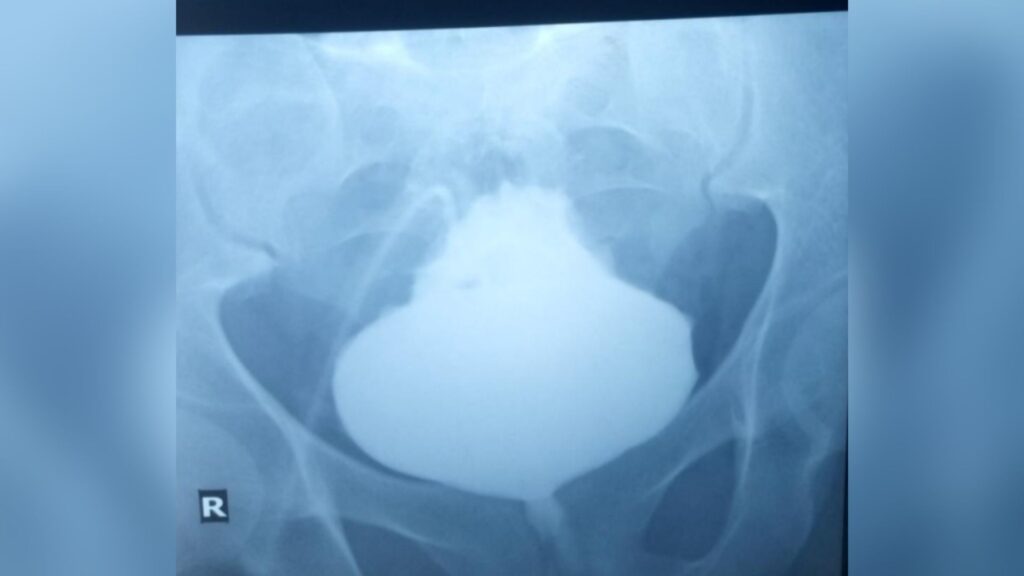

Doctors referred the patient to radiology and obtained a scan of the bladder to look for signs of such physical abnormalities. To visualize the bladder on the X-ray scan, the radiologist administered an X-ray sensitive dye through an abdominal catheter. This revealed that the base of the bladder was distended, leaving behind a pointed tip.

Diagnosis: This condition is known as a “Christmas tree” or “pinecone” bladder because of its appearance.